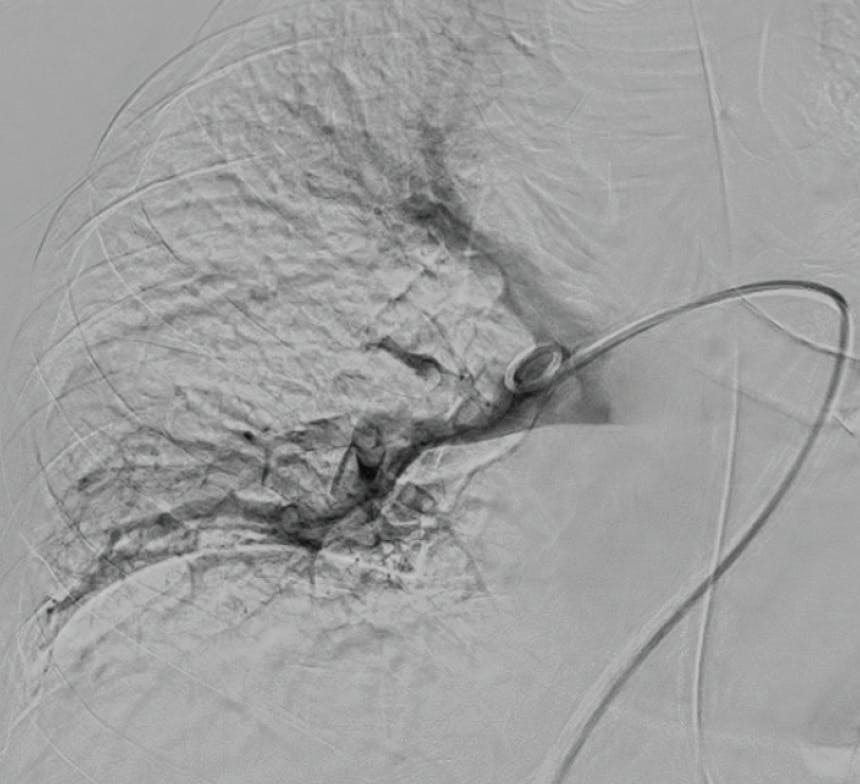

Figure 1. Right initial angiogram.

Figure 2. Left initial angiogram.